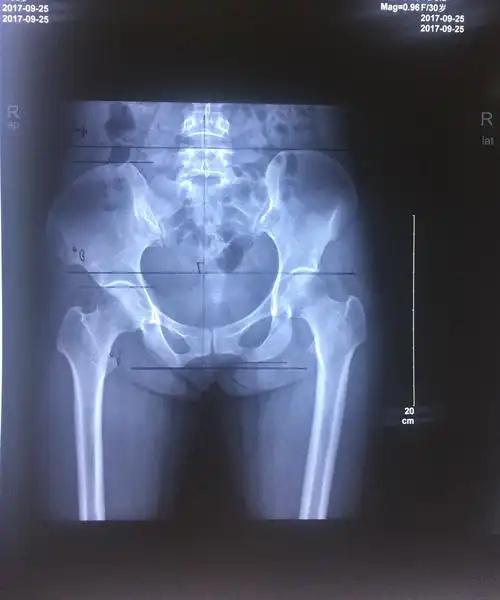

患者非常痛苦x光片提示:骨盆平衡失调,右侧髂骨前旋,导致右侧腿长分析